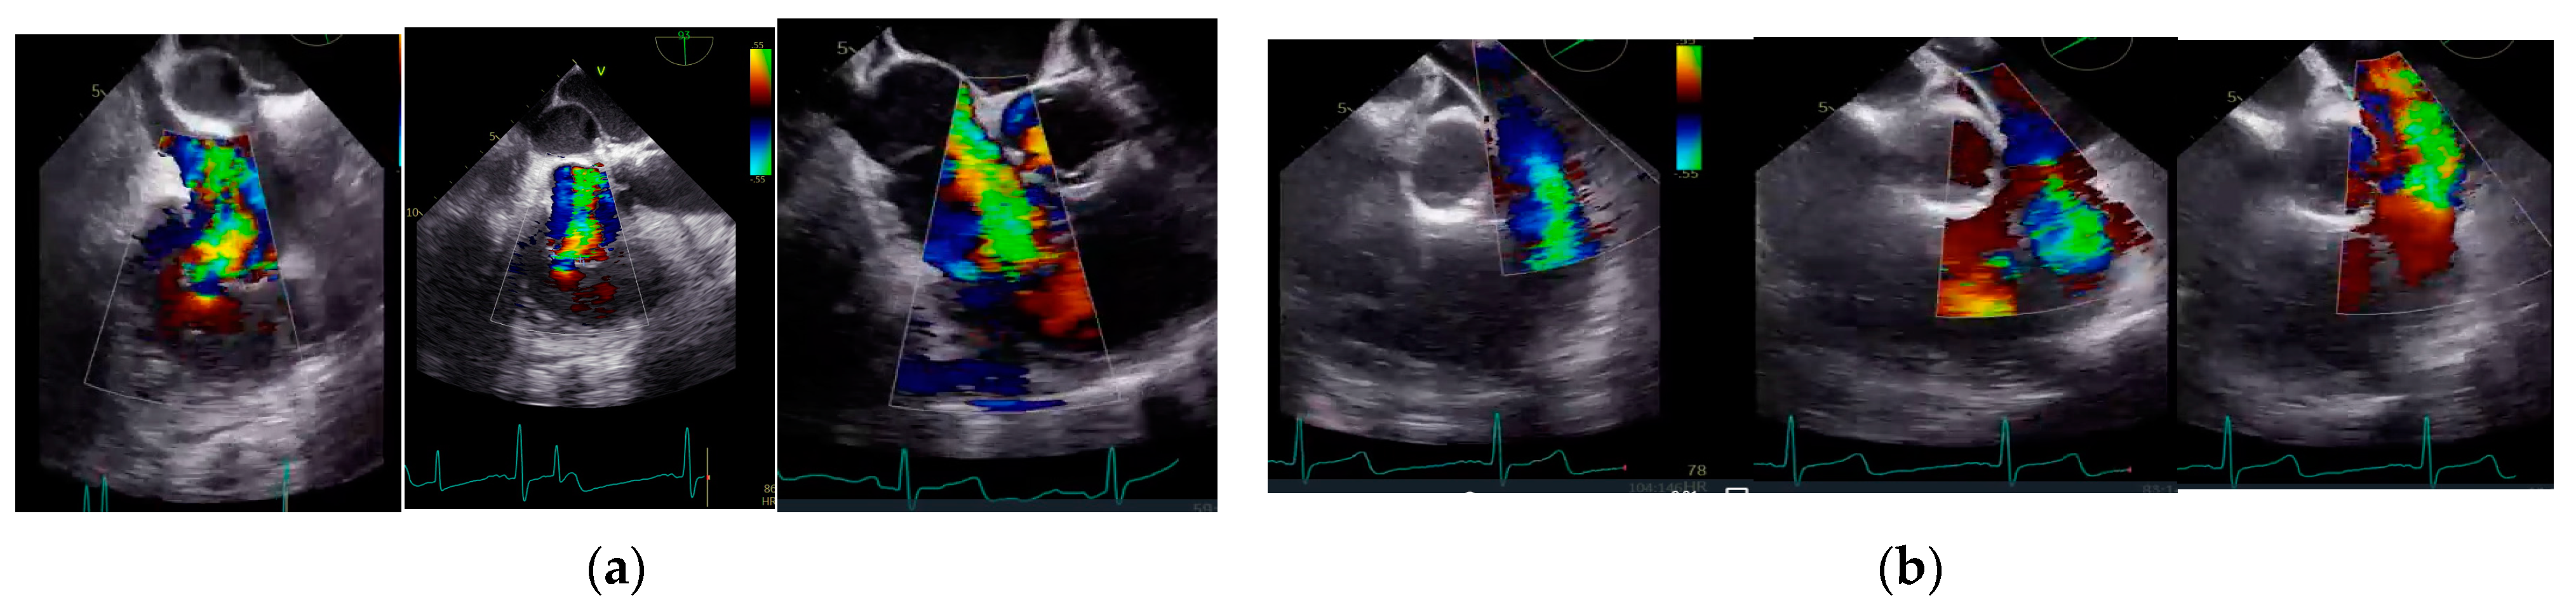

2.4. Echocardiographic Analysis